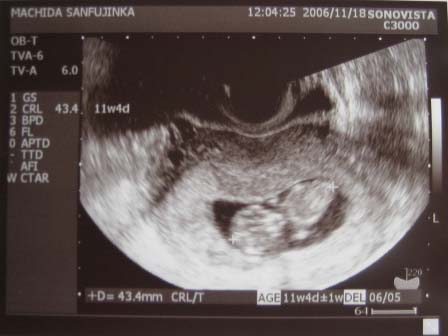

検診の時、ちょうど目の前にモニターがあって、超音波の画像がみれるのですが

ベビちゃんがぐるぐる

ぐるぐる動いてる

というか、回転?してた

「赤ちゃん元気だね~」って先生の一言。

私にもはっきり分かったので、「すごい!すごい!」を連発してしまいました

今日は10週5日ですが、ベビちゃんは11週4日サイズ

だいたい4センチ3ミリくらいのおっきさです。

「ちょっと大きめですね」とのことですが、元気に育ってます